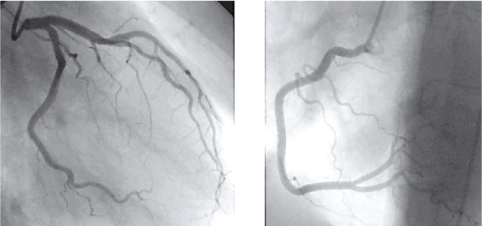

A 28-years-old woman was treated with i.m. injection of phloroglucinol for acute abdominal pain. A few minutes after administration of the drug, the patient had sudden chest discomfort and pain in the left arm, shortness of breath, sweating and palpitations, generalized erythema and cutaneous rashes that justified admission to Emergency Room. On physical examination, arterial blood pressure was 95/70 mmHg and pulse rate was 105 beats/min. Cardiovascular auscultation demonstrated no additional heart sounds. A clean reduction of arterial oxygen saturation was present. Blood tests revealed troponin I value of 2.5 ng/ml. White cell count was 15.51 × 109/l; C-reactive protein was 168 mg/dl. 12-leads ECG evidenced sinus rhythm and S-T depression (2 mm) in leads II, III, aVF (Figure 1). Treatment for anaphylaxis was started, with intravenous administration of hydrocortisone, diphenhydramine and bronchodilators, followed by improvement in cutaneous rashes, dyspnea, erythema and chest discomfort. 2D echocardiography did not reveal any valvular disease or contractility disorders, Simpson's %EF also was within normal limits. Normal ejection fraction, along with absence of wall motion abnormalities or contractile dysfunction was confirmed via 3D transthoracic echocardiography (Figure 2). Afterwards, the patient was transferred to the Coronary Intensive Care Unit due to a diagnosis of acute coronary syndrome and subsequently received 300 mg of ASA, 300 mg of clopidogrel and atorvastatin 40 mg PO. At the preangiographic treatment, 5000 IU heparin was given intravenously. Next, the patient underwent cardiac catheterization for coronary angiography. The procedure revealed no significant stenosis in the left anterior descending artery and its branches, circumflex artery or right coronary artery (Figure 3). On the basis of angiographic findings, a diagnosis of pure vasospasm was considered likely [4], and a diagnosis of KS was made on account of cutaneous and respiratory symptoms which resolved after bronchodilators, hydrocortisone and diphenhydramine. Prior to discharge, the repeat ECG revealed resolution of S-T segment depression, while troponin returned to normal values. Subsequently, the patient was discharged on day five of hospital admission.

Figure 3: Angiography - Normal left and right coronary arteries. View Figure 3